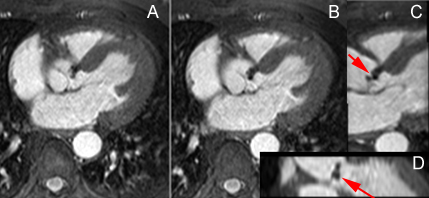

– Il importe de bien connaitre la séméiologie propre aux séquences dont on dispose pour apprécier les jets de perte de signal liés aux flux rapides en séquence ciné.

– Insuffisance aortique : recherche de bicuspidie et quantification de la fraction de régurgitation par l’IRM sont fiables.

– Rétrécissement aortique : Recherche de bicuspidie fiable, possibilité de quantification de la surface valvulaire et du gradient systolique.